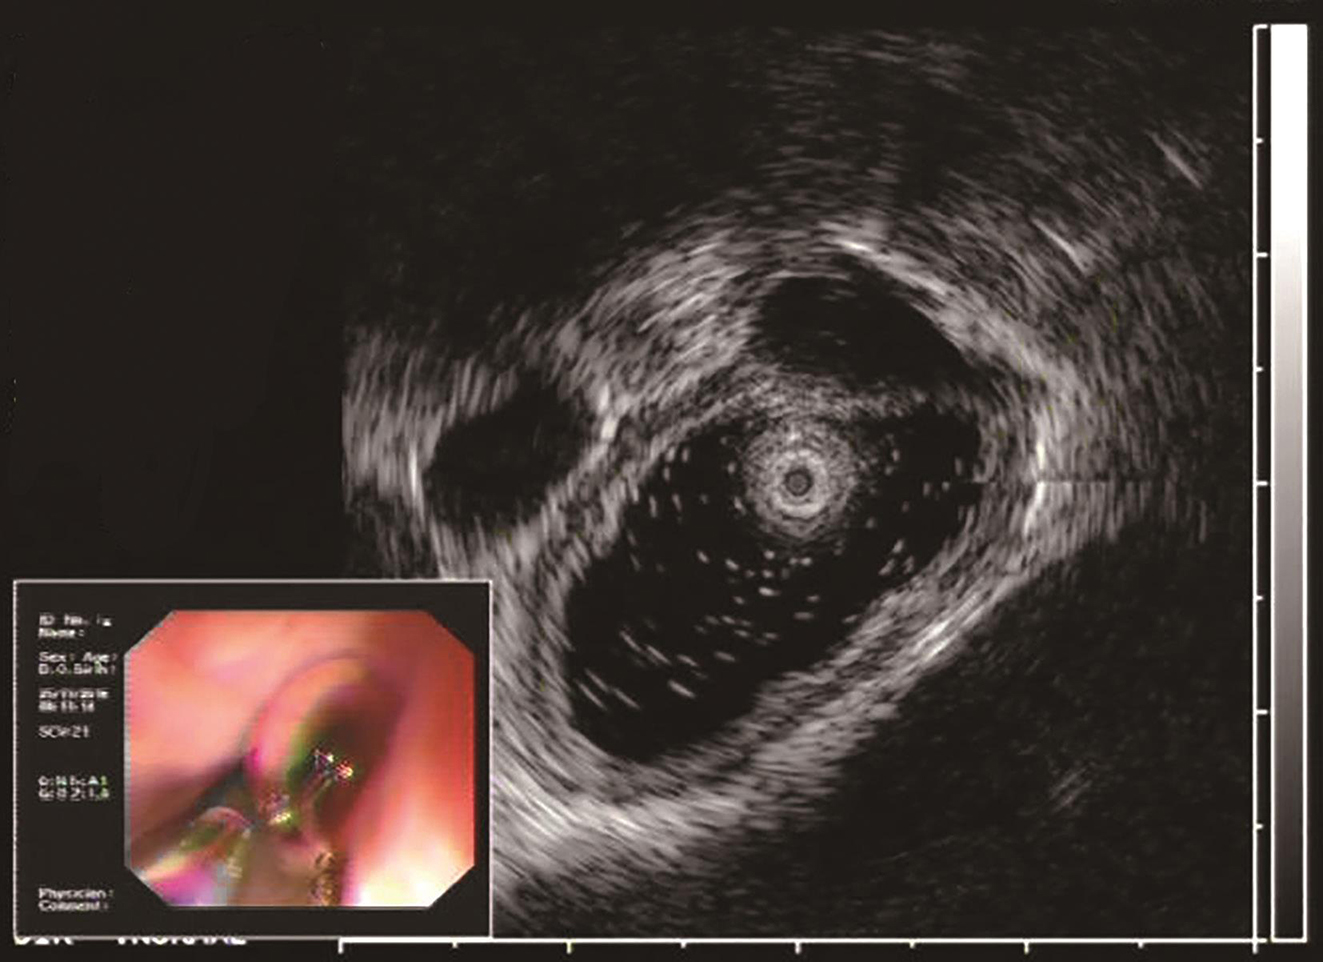

2016年11月于华中科技大学同济医学院附属协和医院门诊行胃镜检查示:距门齿33cm见约1.1cm隆起,表面光滑。超声内镜示(图1)病变位于固有肌层,低回声,边界清晰,大小约1.1cm×0.7cm。遂以“食管固有肌层隆起性病变”收入消化内科。

图1 超声胃镜检查